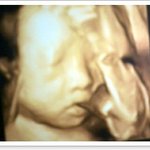

울

연두

입체초음파 사진~^^

(5)

연두맘

|

08.07.09 19:36